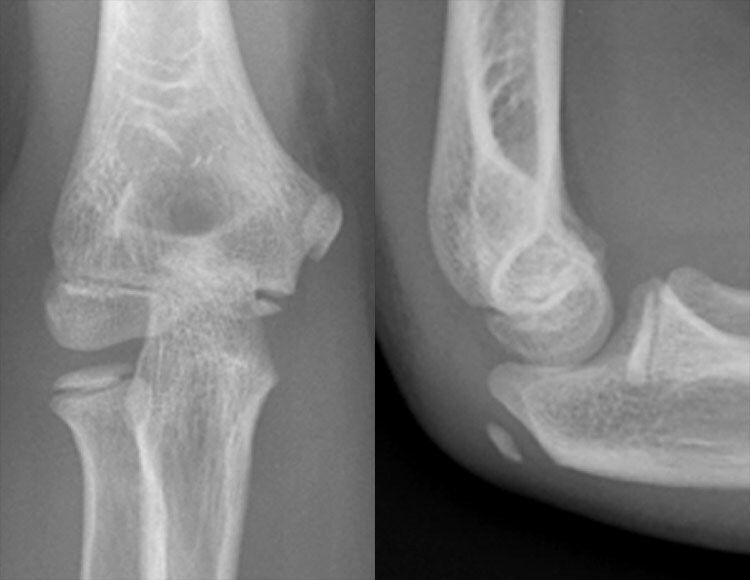

X-RAY QUIZ: Which finding is present on this image?

A: Normal X-ray image

B: Sail sign

C: Meniscus sign

D: Pneumothorax

E: Air bronchogram

Start Quiz bit.ly/36i1txn